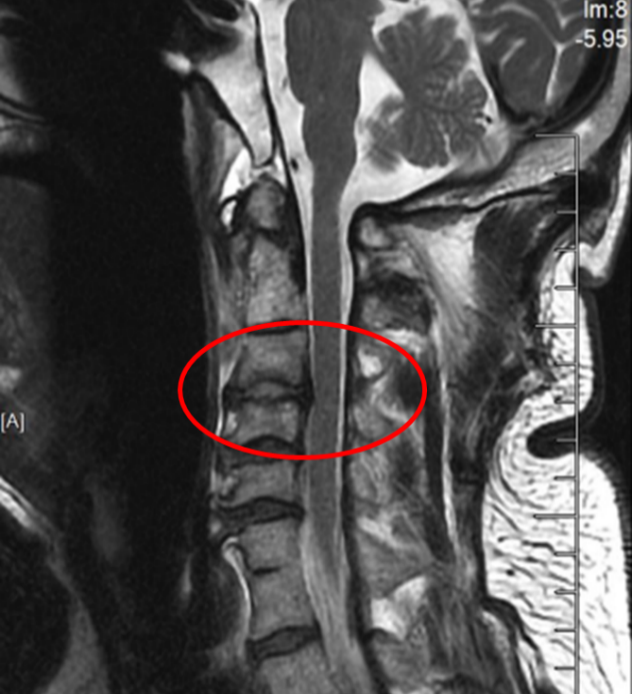

图2:术后正侧位片

在麻醉手术科的严密监护下,刘义杰副主任医师首先熟练地完成了颈椎前路C3-4减压融合术(ACDF),成功解除了脊髓的压迫。然而,通过同一个仅3厘米的微小切口,精准地将螺钉植入游离且向后倾倒的齿状突具有极大的挑战性。关键时刻,骨科手术机器人发挥了“超级助手”的作用。团队利用机器人导航系统,对进钉点和角度进行了反复测算与调整,导针精准抵达目标。随后,由姜为民主任专利研发的一枚新型齿状突螺钉顺着通道顺利旋入,牢牢锁住了骨折端。整个过程出血量少,手术顺利完成。

此次手术的成功凝聚了苏大附四院脊柱外科团队多年来在上颈椎领域的深耕细作,是“微创理念”与“智能科技”完美融合的典范。特别是姜为民主任专利研发的新型齿状突螺钉,通过小切口实现了传统开放手术难以企及的精准与安全,兼具微创与稳固的双重优势,为此类疾患治疗带来更佳的方案选择。